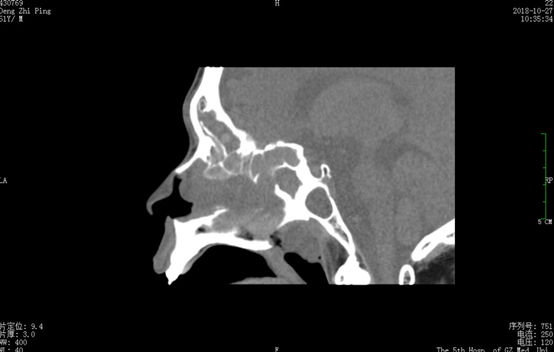

张主任带领耳鼻咽喉科医护团队在经过周密的手术期治疗计划制定和精心的术前准备后,在与麻醉科、呼吸内科、心血管内科、ICU、医学影像科等相关科室联合会诊,在术前详细阅读鼻窦CT片时,却发现吴叔鼻腔、鼻窦解剖异常,追问病史才知道吴叔在车祸前曾做过鼻腔鼻窦手术。

△吴叔术前CT矢状位图